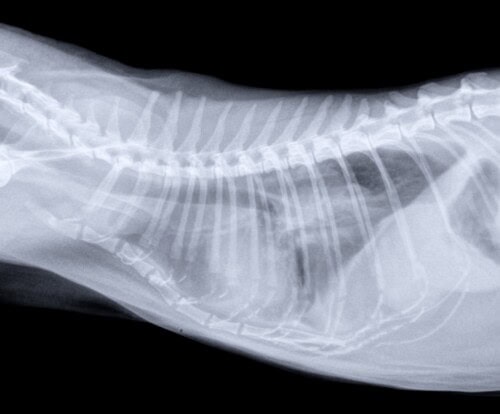

Photos 4 et 5: Radiographies thoraciques (profil et face dorso-ventrale)

La récupération post-opératoire est bonne et la chatte remarche normalement. Une nouvelle radiographie thoracique au retrait des fils ne met toujours pas en évidence de lésion pulmonaire primitive.

De nouvelles radiographies révèlent alors des lésions ostéolytiques identiques de la dernière phalange de ce doigt III de l’antérieur droit, mais surtout la présence d’une masse tissulaire dans les lobes caudaux, compatible avec une tumeur pulmonaire. Aucun signe respiratoire n’est présent.

Photo 10 : Radiographie thoracique de profil droit.

Présence d’une masse pulmonaire dans les lobes caudaux

– La radiographie thoracique permet presque toujours (plus de 90 % des cas) de mettre en évidence une ou plusieurs masses pulmonaires révélatrices de la tumeur primitive, avant même la survenue de signes respiratoires. Dans notre expérience, avant le cas présenté ici, tous les chats diagnostiqués avec des métastases digitées de métastases pulmonaires présentaient une masse volumineuse dans les lobes caudaux, dès l’apparition des signes liés aux métastases (boiterie, gonflement du doigt, chute de la griffe …). Par son seuil de détection beaucoup plus bas que la radiographie, un examen tomodensitométrique thoracique aurait peut-être permis de détecter cette tumeur pulmonaire.